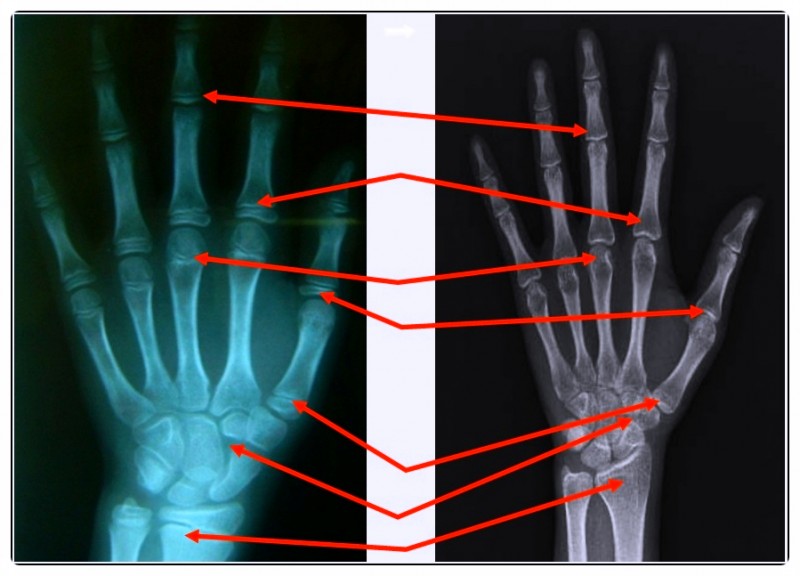

성장 진단의 첫걸음은 ‘정확한 평가’입니다.

단순히 키와 체중만 보는 게 아니라, 성장판의 상태와 성조숙증 가능성, 비만 여부까지 함께 확인합니다.

성장판이 얼마나 남아 있는지에 따라 앞으로의 성장 가능성을 예측할 수 있습니다.

또래보다 체중이 빠르게 늘거나 비만인 경우, 성장판이 빨리 닫힐 위험도 커지죠.